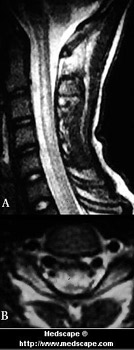

Figure 4. MRI showing juxta-articular avascular osteonecrosis of the hip. Reprinted with permission from the Virtual Hospital. La MRI mostra osteonecrosi avascolare vicino all’articolazione dell’anca.

La risonanza magnetica (Magnetic resonance imaging – MRI) (Fig.4) riesce ad individuare precocemente le lesioni, ma costosa generalmente non rientra tra gli esami di screening per una ampia popolazione. Fu usata nel 1981 dal Decompression Sickness Registry, il quale ha rilevato che la percentuale di necrosi, sia articolare che ossea, aumenta in un campione di subacquei con l’età e con l’esperienza.

Da ciò si può supporre che esaminare dei subacquei “profondisti”con MRI può aiutare a diagnosticare lesioni articolari e a prevenirne il collasso. ( 9)